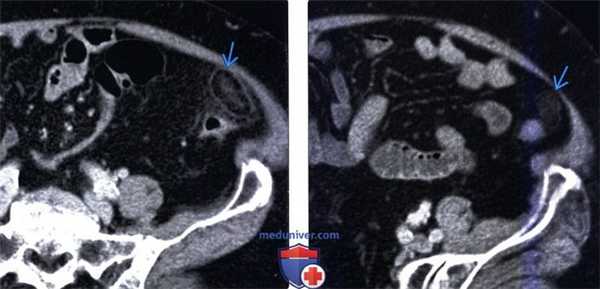

(Слева) На аксиальной КТ у пациента с узелковым полиартериитом и болью в животе определяется помутнение жировой клетчатки в передних отделах сальника, соотносящееся с локализацией боли. Это проявление инфаркта сальника, вероятно, обусловлено васкулитом.

(Справа) На аксиальной КТ с контрастным усилением у одиннадцатилетнего мальчика с жалобами на боли в правом нижнем квадранте (живота) визуализируется четко очерченное, овоидной формы, жировой плотности объемное образование в правом нижнем сегменте, с помутнением прилежащей жировой клетчатки. Лечащий врач склонялся к диагнозу аппендицита, при оперативном вмешательстве был обнаружен инфаркт сальника.

3. КТ при аппендажите:

• КТ с контрастным усилением:

о Овоидное образование одинаковой плотности с околоободочной жировой клетчаткой размерами о Оказывает местный эффект объемного образования на прилегающую стенку кишки

о Симптом центральной точки: центральный очаге повышенным коэффициентом ослабления, представляющий собой центральный застойный или тромбированный сосуд и/или зону центрально кровоизлияния

о Симптом пояска с высоким коэффициентом ослабления: окружающий овоидное образование ободок повышенной плотности шириною 2-3 мм, представляющий собой воспаленную висцеральную брюшину

о Воспалительные изменения окружающих тканей: исчерчен-ность жировой клетчатки, утолщение париетальной брюшины и легкое локальное утолщение прилегающей кишечной стенки

(Левый) У этого же пациента при КТ с контрастным усилением на аксиальной томограмме определяется типичная рентгенологическая картина аппендажита с исчерченностью окружающей жировой клетчатки. Обратите внимание на отсутствие изменений прилегающей сигмовидной кишки.

(Правый) При мульти планарной реконструкции в соответствующей корональной плоскости определяется воспаленный сальниковый при весок; видна его тесная связь с неизмененной прилегающей сигмовидной кишкой.

(Левый) У пациента с подозрением на дивертикулит при КТ с контрастным усилением определяется образование, содержащее жировую клетчатку, периферия образования характеризуется повышенным коэффициентом ослабления (симптом кольца), в центре визуализируется линейный участок повышенной плотности (эквивалент симптома центральной точки в проекции еп face). Обратите внимание на исчерченность окружающей жировой клетчатки.

(Правый) Этот же пациент. Контрольное КТ с контрастным усилением восемь месяцев спустя. Отмечается улучшение, но рентгенологические изменения все еще сохраняются. Этот случай иллюстрирует медленное разрешение рентгенологических изменений при аппендажите.